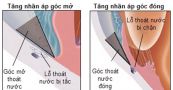

Bệnh tăng nhãn áp góc đóng nguyên phát là một loại bệnh ngăn chặn hệ thống thoát nước mắt qua lưới sợi mô liên kết, bao gồm bệnh tăng nhãn áp góc đóng cấp tính và tăng nhãn áp góc đóng mạn tính. Cùng eLib.VN tìm hiểu bài viết dưới đây để hiểu rõ hơn về bệnh lý này nhé!

Tăng nhãn áp góc đóng cấp tính là một tình trạng vô cùng nghiêm trọng khi áp lực bên trong mắt (áp lực nội nhãn, nhãn áp hay IOP) tăng đột ngột, xảy ra khi dòng thủy dịch bị chặn lại không chảy ra ngoài được. Trường hợp này cần được điều trị khẩn cấp, nếu không có thể dẫn đến mất thị lực vĩnh viễn. Để biết rõ hơn về bệnh lý này, mời các bạn tham khảo bài viết dưới đây.

Tăng nhãn áp còn có các tên gọi khác như: bệnh thiên đầu thống, cườm nước và glocom. Đây là một bệnh về mắt thường gặp. Do tăng áp lực nhãn cầu nên người bệnh nhìn mờ và đau đầu. Nếu áp lực nhãn cầu cao kéo dài sẽ chèn ép làm tổn thương thần kinh thị giác phía sau và có thể gây mù lòa nếu không được chữa trị kịp thời. Có nhiều nguyên nhân gây bệnh, do đó sẽ có các phương pháp điều trị khác nhau tùy theo bệnh sinh. Cùng eLib.VN tìm hiểu bài viết dưới đây để hiểu rõ hơn về bệnh lý này nhé!